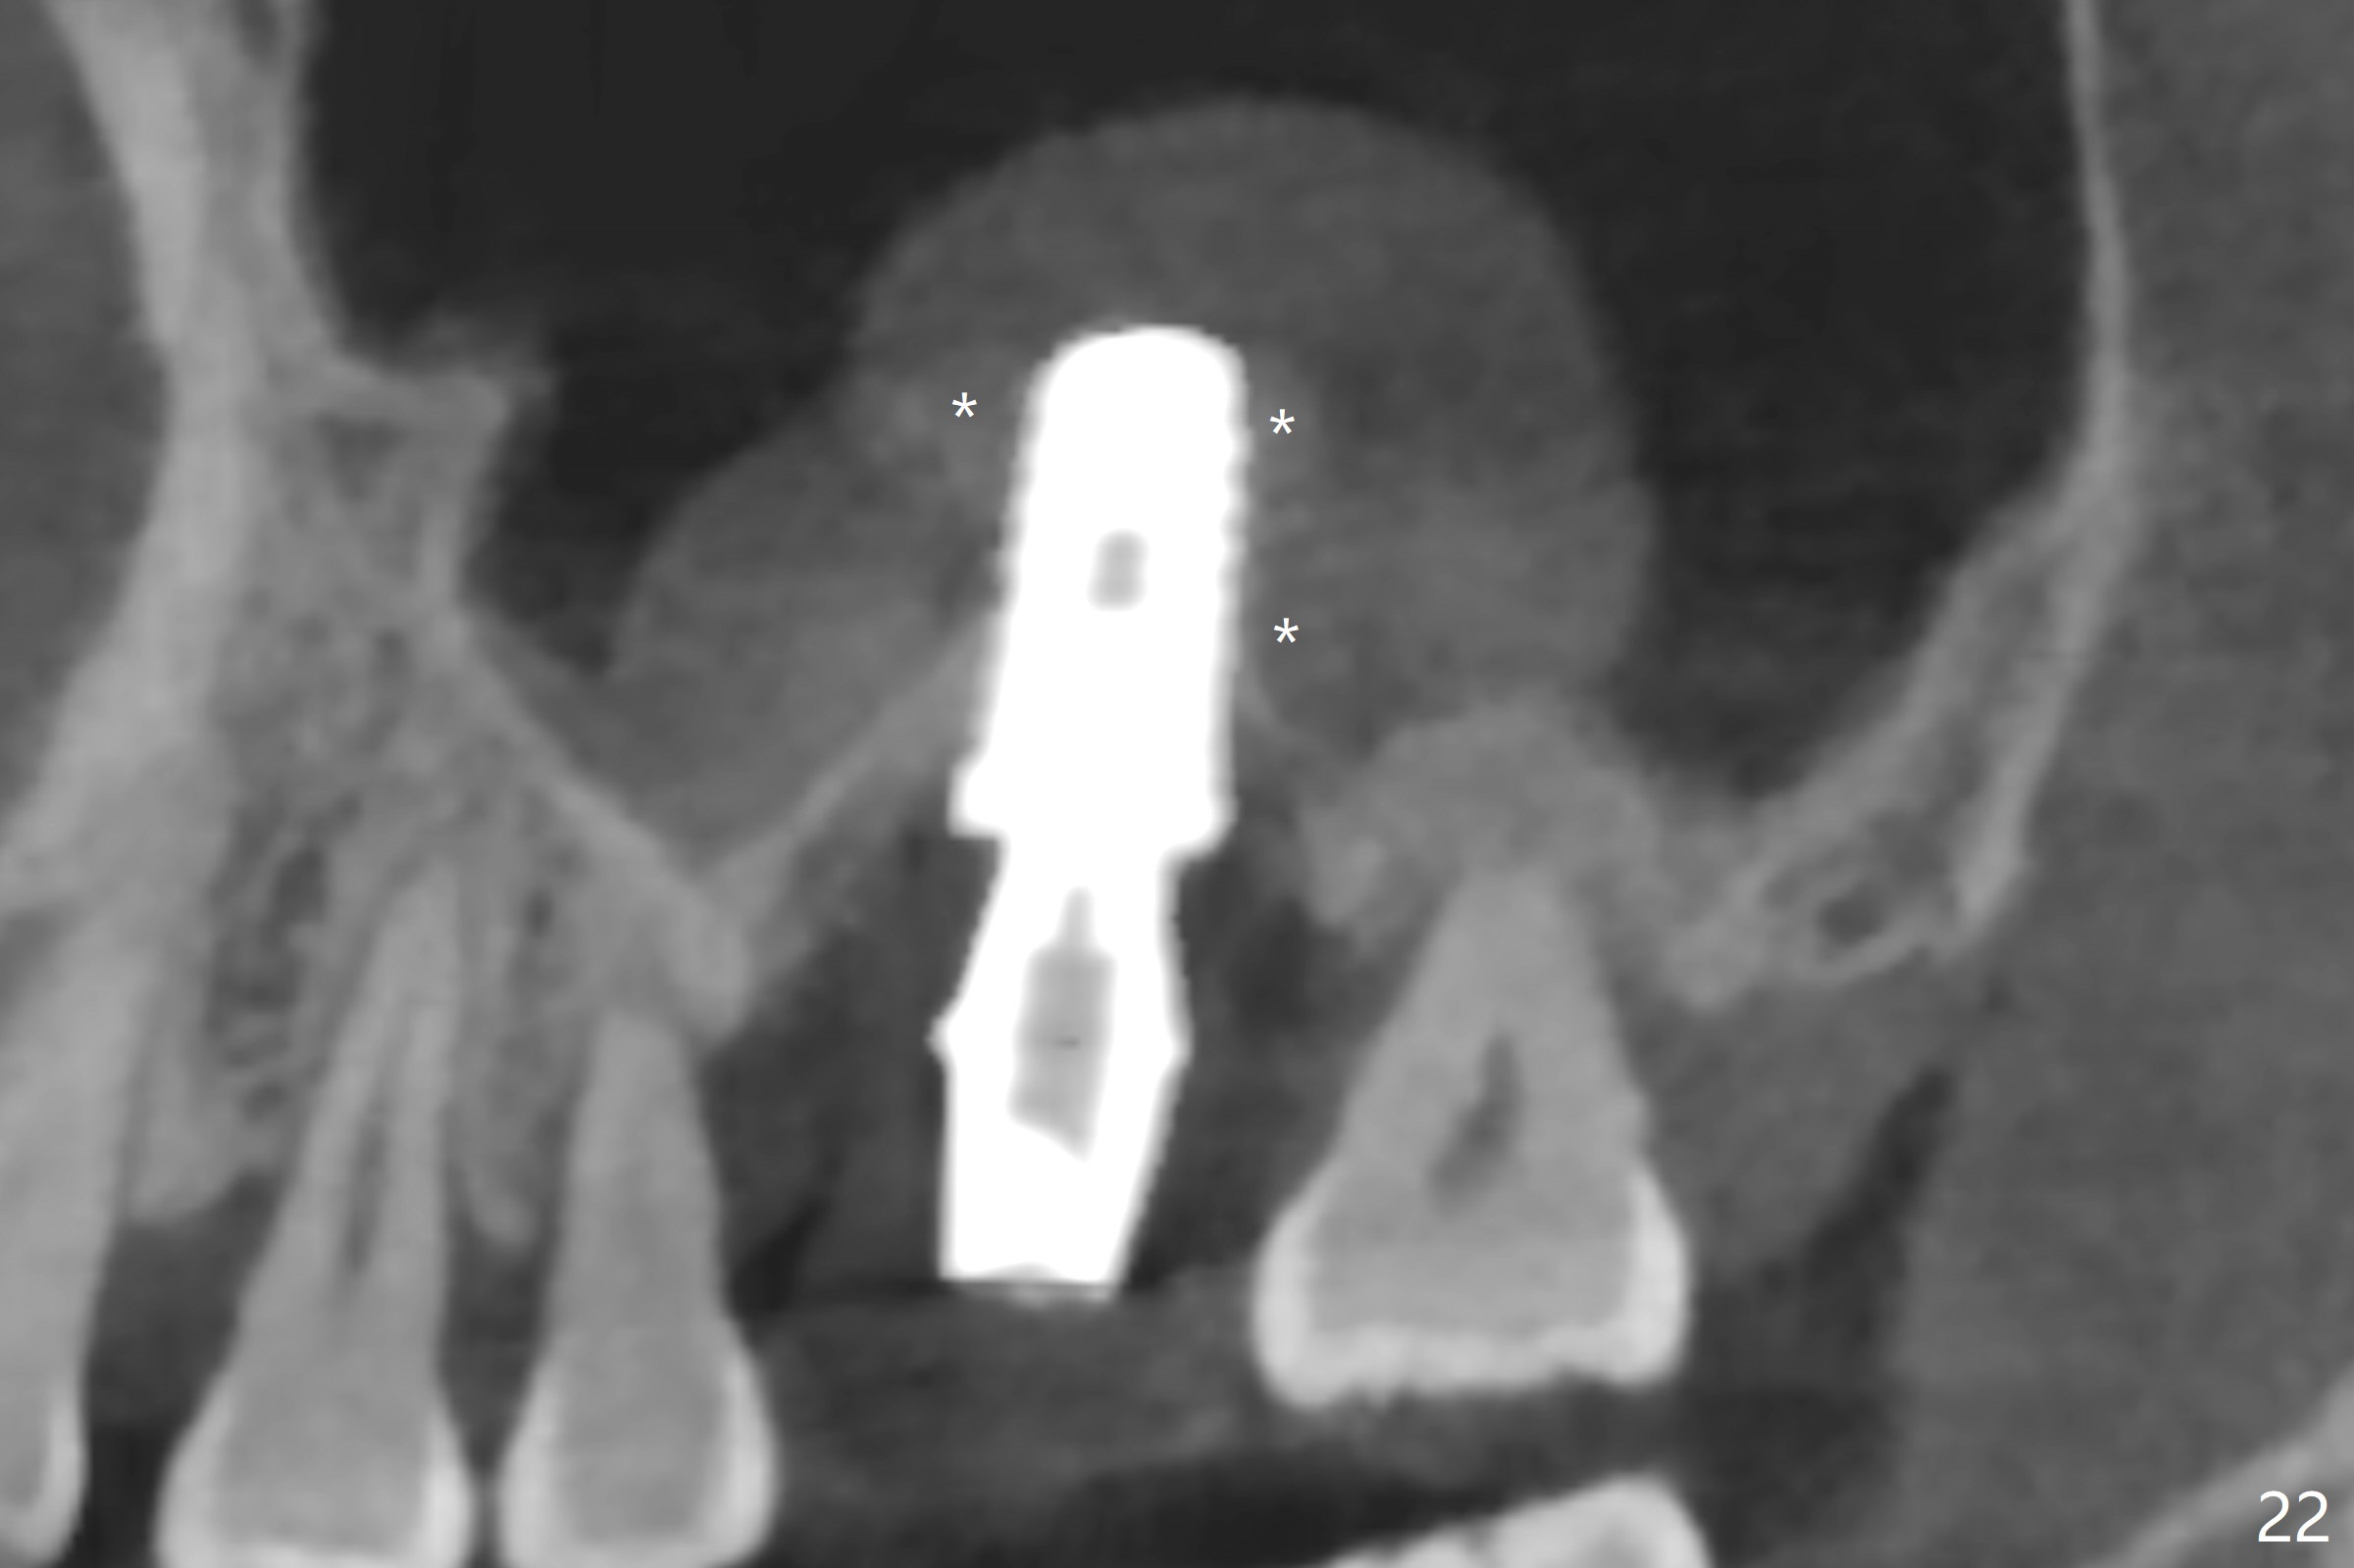

There is a mushroom around the implant nearly 5 months postop/immediately before cementation (Fig.21).  The bone density around the implant is low (Fig.22-24' *).